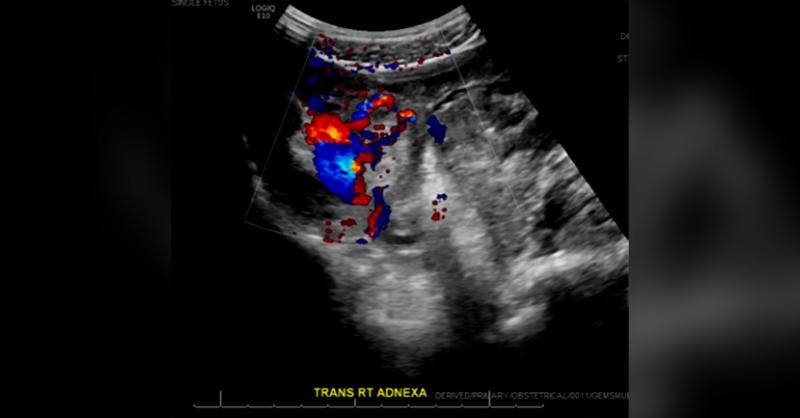

- A 22-year-old Woman with Partial Molar Pregnancy

Hydatidiform moles are abnormal gestations occurring mainly due to abnormal fertilization and are subclassified into either partial molar or complete molar pregnancies. (1) The classification is based on morphology, pathology, and genetic differences. Complete molar pregnancies usually carry the paternal genomic origin, 46 XX, and result due to the